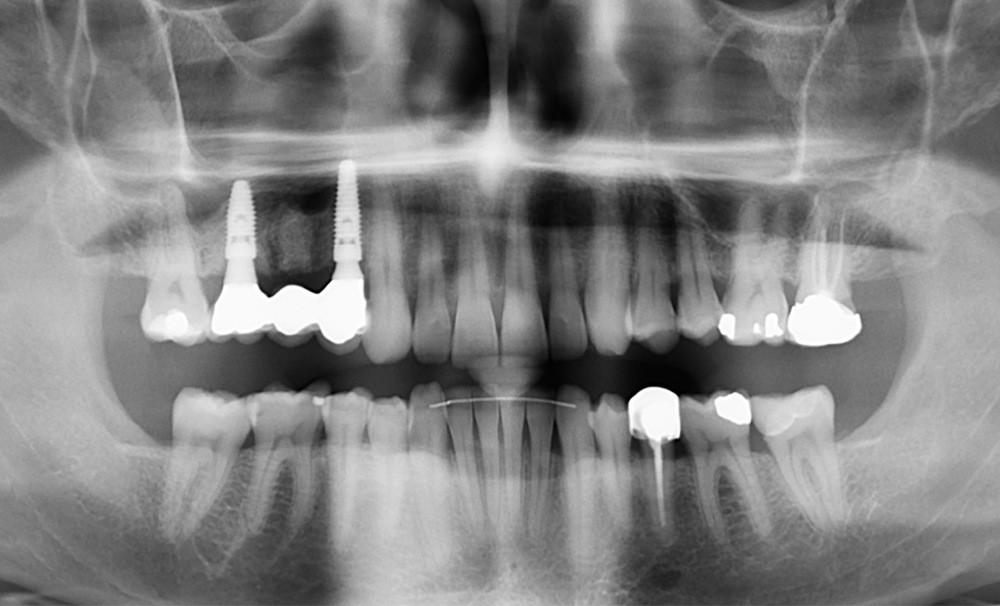

Le plan de traitement établi conjointement avec son chirurgien-dentiste traitant consiste à réaliser un alignement dentaire mandibulaire et à réaliser des extractions de 16 et 15 pour un remplacement par prothèse implanto-portée.

Un accompagnement par des meulages occlusaux est réalisé.

Les techniques orthodontiques de déplacement par gouttières orthodontiques thermoformées sont très efficaces pour gérer des situations simples. Ce patient en montre l’intérêt, en particulier lorsque la forme d’arcade dentaire doit être maintenue. Les systèmes « in-office » peuvent tout à fait permettre la gestion de ces situations.